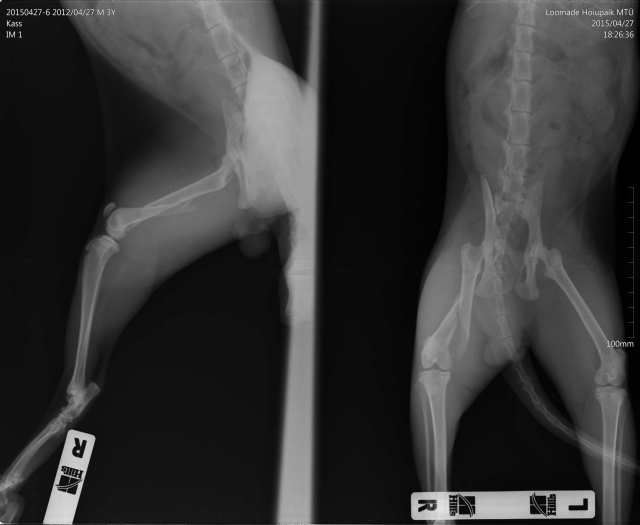

Kass kukkunud ilmselt aknast alla, tagumise käpa luumurd.

kiisu pareneb. Tal oli puusaluu murd (unustasin pildid lisada siia albumisse, kohe teen).